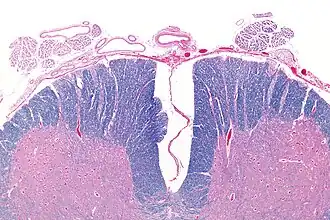

![]() Micrograph showing an axial section of the anterior spinal cord and anterior spinal artery (top-middle of image). LFB-HE stain. | |